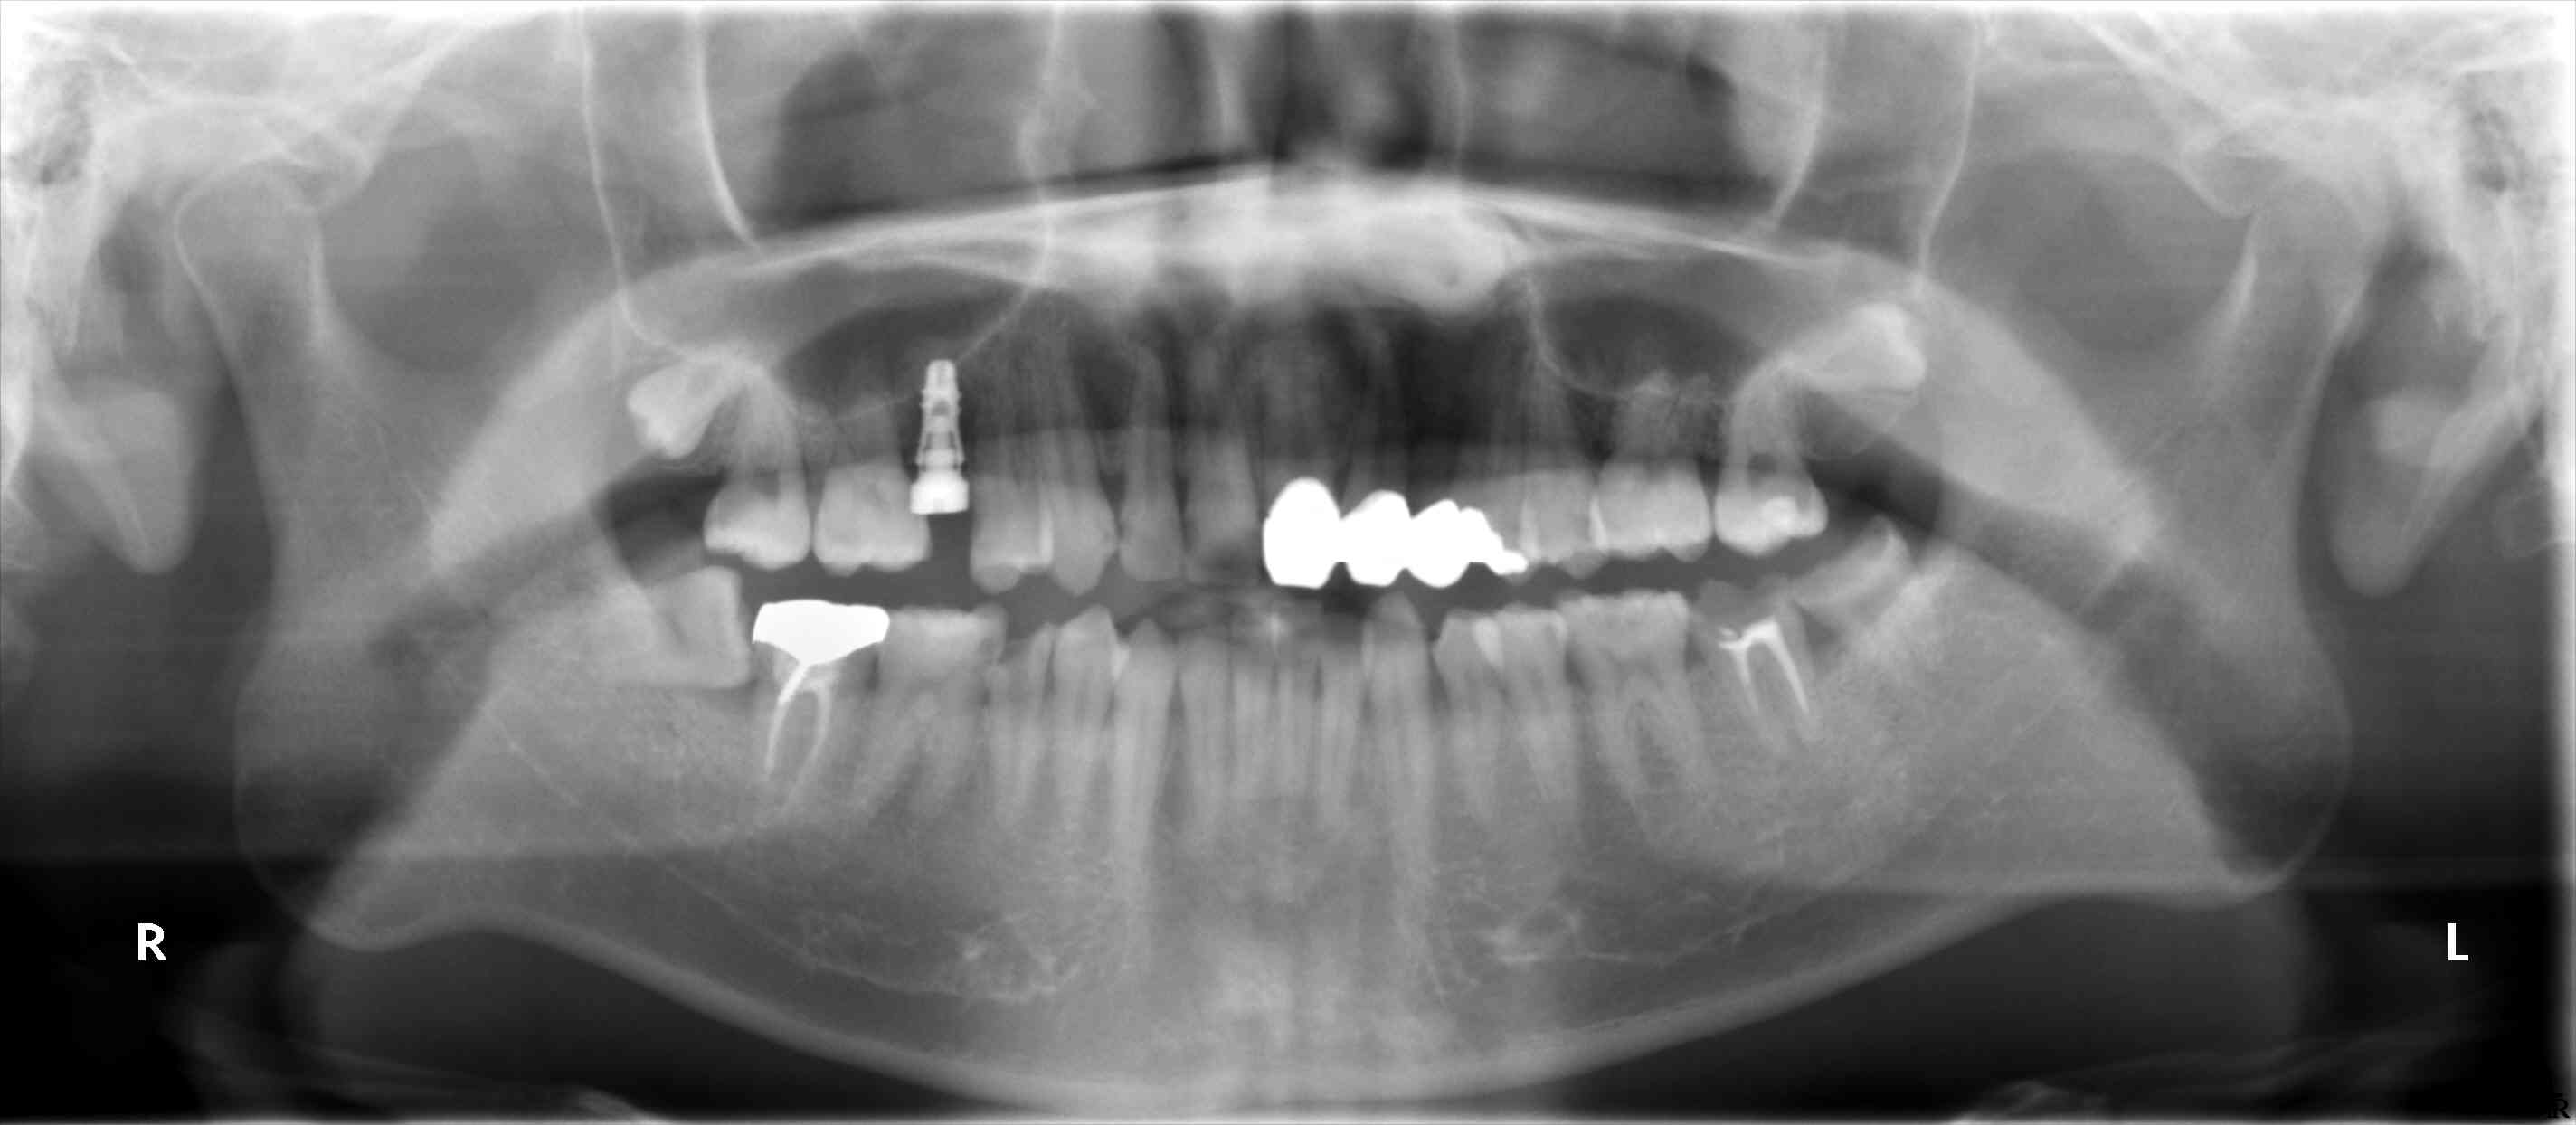

術後のパノラマで、シュナイダーメンブレンが挙上されているのが確認できます。

埋入後のパノラマです。

近遠心では、やや骨縁下になっています。

プラットフォームシフト用のヒーリングアバットを装着しています。